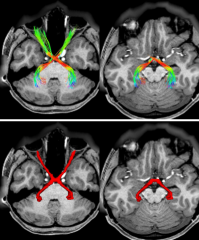

Refer to caption

Figure 3: Examples of the CN pathway reconstruction results using the proposed CN atlas on HCP dataset and MDM dataset. The tractogram is color-coded in average directional color using the ’Color Fibers By Mean Orientation’ buttons of the TractographyDisplay Module of the 3D Slicer.

To demonstrate the identification performance of the proposed CN atlas, we select different CN tracts from different subjects of the HCP dataset and the MDM dataset for qualitative comparison. Fig. 3(a) gives the CN pathway reconstruction results of subjects #100206, subjects #103414, subjects #107422, subjects #110613 and subjects #123117 using the proposed CN atlas on the HCP dataset, respectively. Fig. 3(b) shows the CN pathway reconstruction results of subjects #001, subjects #002, subjects #003, subjects #004 and subjects #005 using the proposed CN atlas on the MDM dataset, respectively. The top and bottom rows of Figs. 3(a) and  3(b) provide the 3D views of the identified CNs and displays of the 3D view superimposed on the slice, respectively. The CNs identified by the proposed CN atlas conform to the anatomical shape and fit the anatomical location on the slice.

The proposed CN atlas successfully reconstructed all 5 pairs of CNs (II, III, V, VII/VIII) in individual subjects and achieved a 100% identification rate for manually verifiable CNs across the cohort. Quantitative evaluation revealed strong spatial agreement between automated and manual selection methods [7, 21, 32, 37], with mean CN spatial overlap scores of 0.7448 (HCP subjects) and 0.7827 (MDM subjects)-exceeding the 0.72 threshold recommended by Cousineau et al. [34]. Visual assessment confirmed highly similar fiber trajectories with robust spatial correspondence (Fig. 3). Importantly, these overlap scores are comparable to or exceed those reported for state-of-the-art single-pair CN atlases applied to individual nerves, such as CN II [17], CN III [18], CN V [19], and CN VII/VIII [20]. This demonstrates that our multi-nerve approach achieves similar fidelity without sacrificing accuracy. We further demonstrated the method’s robustness and reliability for CN identification using a dataset of 20 MDM subjects and two PA patients.

We establish the anatomical validity of the proposed CN atlas in recognizing 5 pairs of CNs through multiple lines of evidence. First, the automatically identified CNs show high comparability to manual CN selection results, with visually similar fiber trajectories and strong spatial overlap (Fig. 3). Second, the anatomical validity of automatically recognized CNs was confirmed in patient data. As shown in Fig. 4, when a tumor compressed the optic nerve (CN II) along its pathway between the optic chiasm and lateral geniculate nucleus, our method successfully reconstructed the surrounding nerve fibers. This capability is critical for preoperative tumor resection planning. Finally, intraoperative validation in a CP patient confirmed that automatically identified nerves maintained clear spatial relationships with tumor locations.